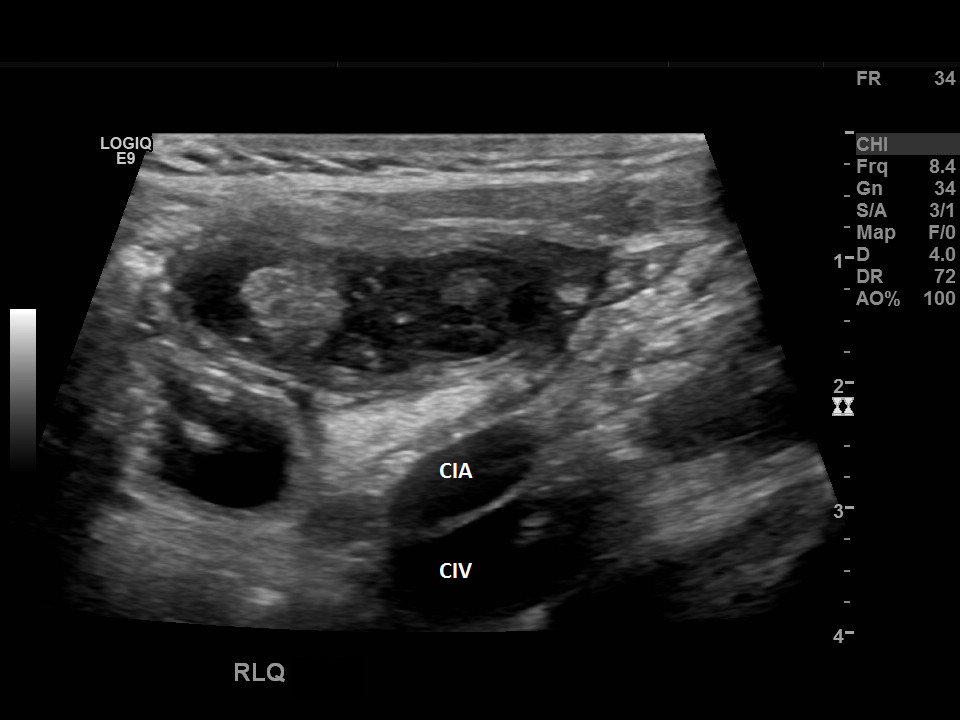

Appendicitis 19

Perforate appendicitis measuring 1.8 cm with interval abscess formation on follow up ultrasound imaging.